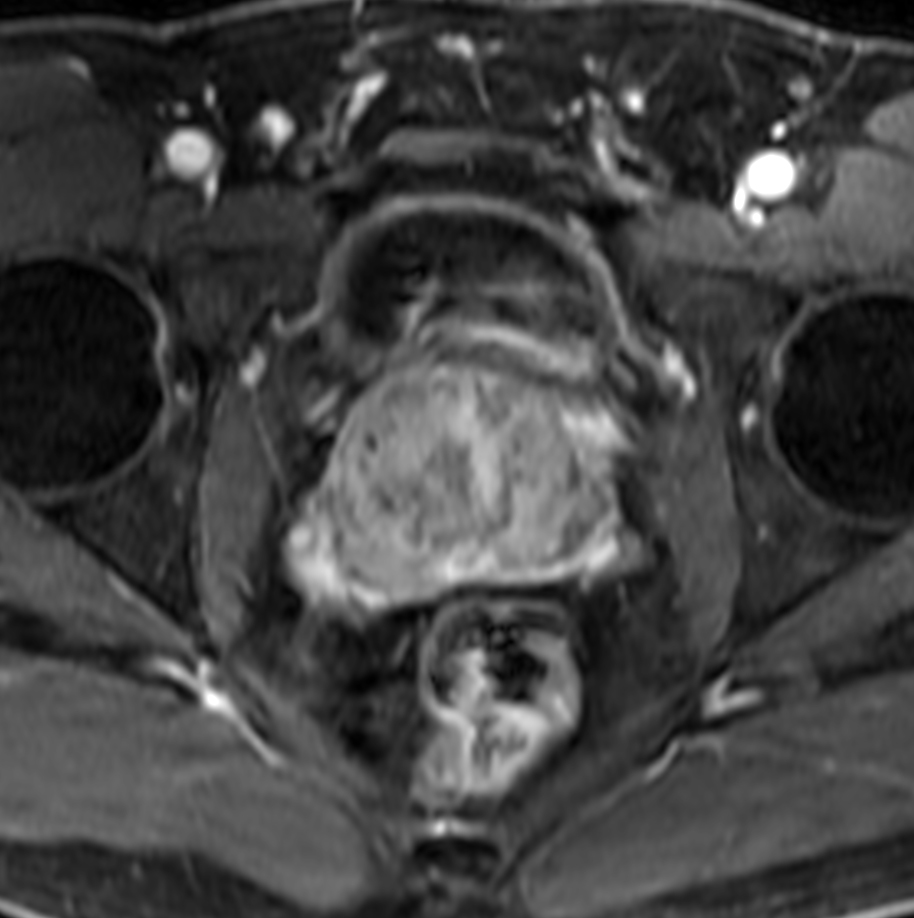

Axial dynamic T1w mDIXON XD with Compressed SENSE